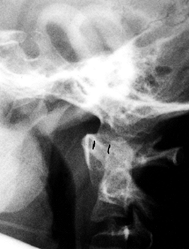

Platyspondyly is present. Odontoid hypoplasia, resulting in

atlantoaxial instability, is common and the surgeon should look for it (152).

![]() |

|

Figure 180.14. Platyspondyly and vertebral irregularities in a 6-year-old boy with Morquio’s syndrome.

Figure 180.15. Odontoid hypoplasia and atlantoaxial instability in a 6-year-old boy with Morquio’s syndrome.